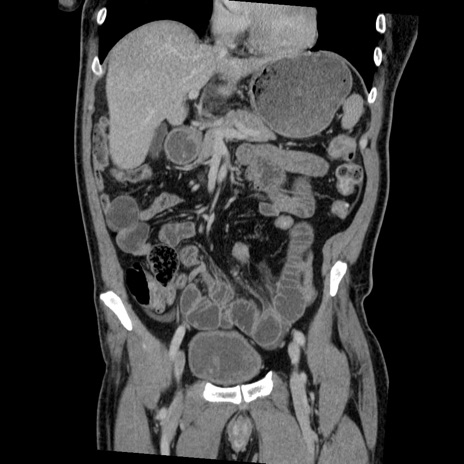

症例22(冠状断像)

【症例】50歳代男性

【主訴】腹痛

【現病歴】AVMからの被殻出血のため回復期リハ病棟入院中。 本日午後3時頃急に下腹部痛が出現した。

【既往歴】AVM、被殻出血、虫垂炎、高血圧

【身体所見】意識晴明、左半身不全麻痺、会話の理解は良好、36.5°C、腹部:膨隆、全体に板状硬、下腹部正中に圧痛点あり、反跳痛-、筋性防御不明、右下腹部にope scar

【データ】WBC 9400、CRP 0.06